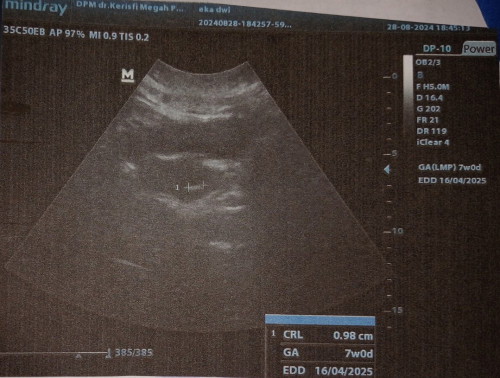

USG di uk 7w

Alhamdulillah, berkembang sesuai usianya. Sudah terlihat janinnya, sama dokternya disuru balik ketika uk 11-12 week untuk lihat perkembangan & detak jantungnya. #Sharing_dong_Bund